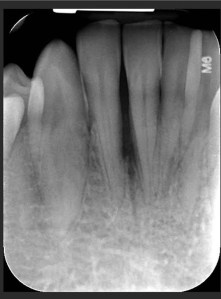

Cazuri clinice